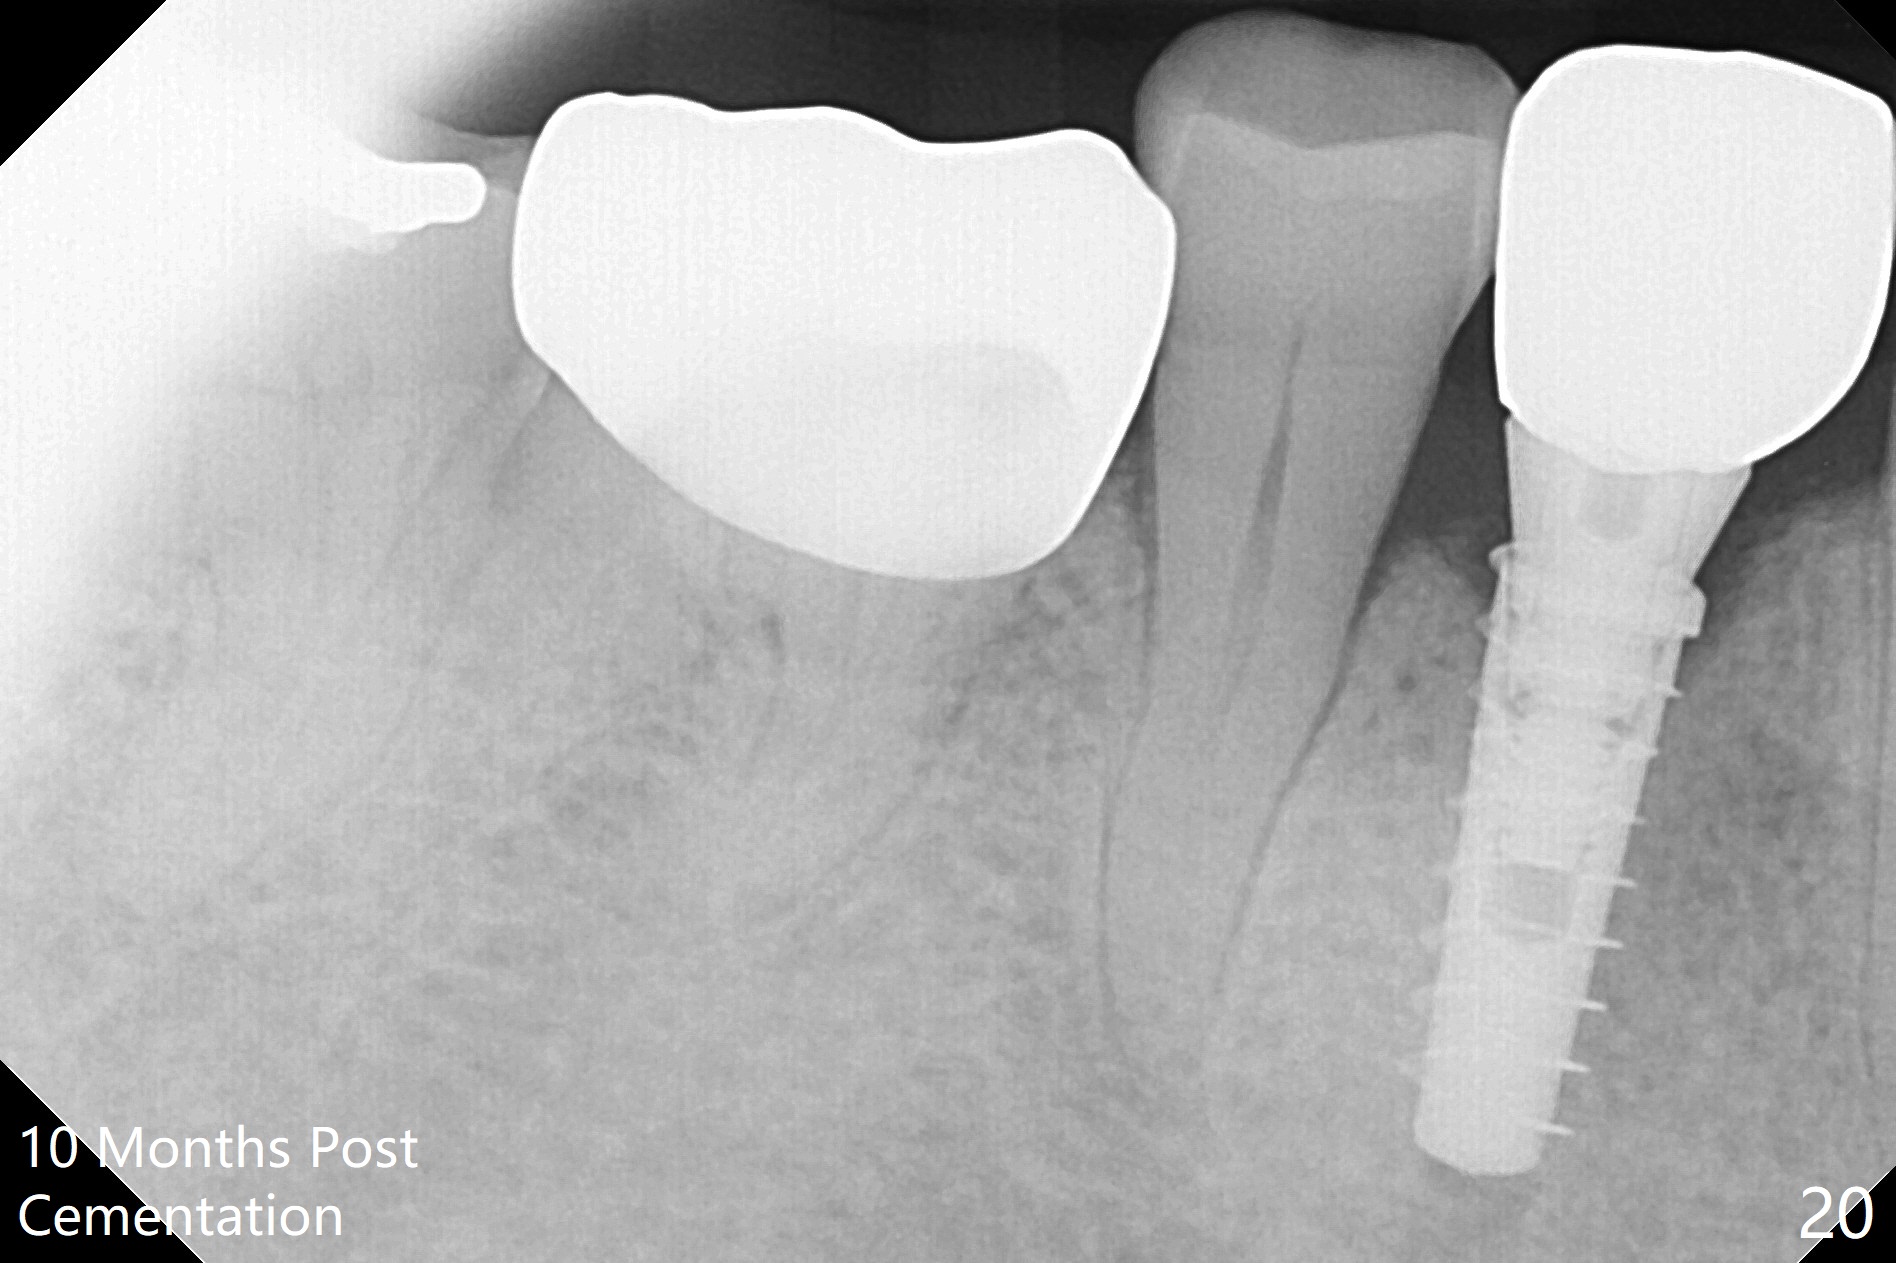

The right posterior final restorations (Fig.14) are fabricated as planned: increase in vertical height (Fig.15). The increase is minimal (Fig.14, 17(#2 limited crown height), 16 (#2 crown being thin *)). Fig.17,18 are taken immediately post cementation. There is no bone loss 10 months post cementation (Fig.19,20). The gingiva is healthy around the implant crowns (#2, 4 and 28) 1 year 4 months post cementation (Fig.21,22).